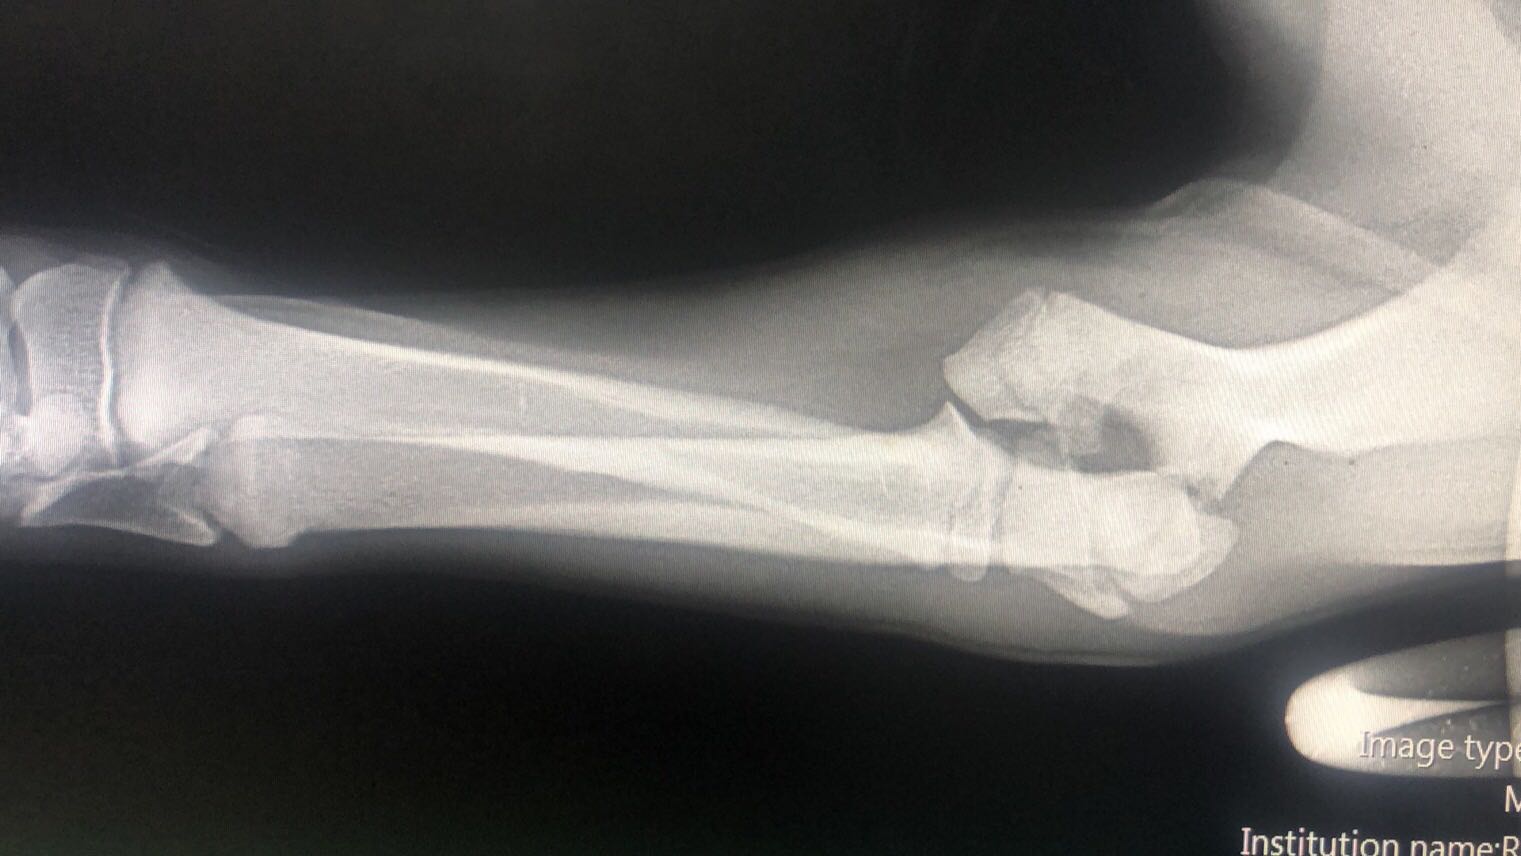

惨22岁小伙国外断骨增高手术失败回国治疗恐终身残疾

图片尺寸659x335